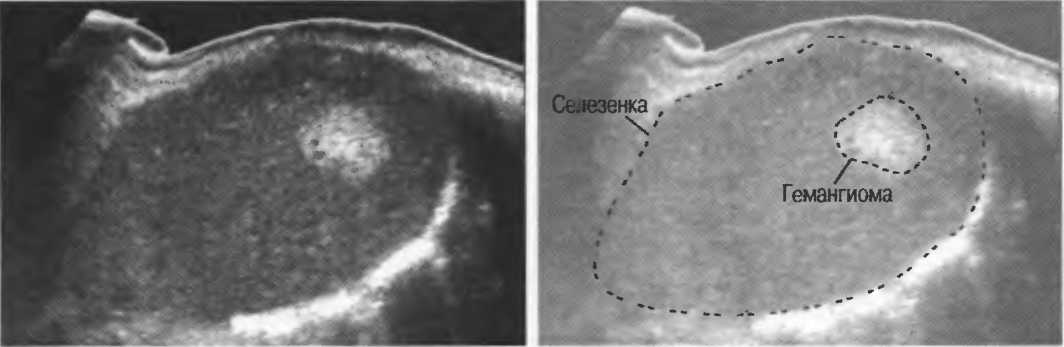

Хирургические процессы при эмболизации гемангиомы на фото

Раздел: Снимки-откровения